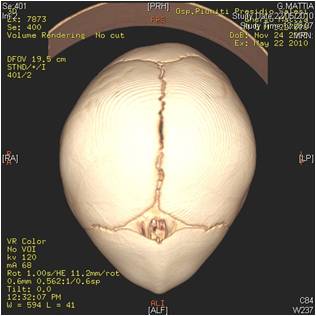

Correzione malformazioni cranio-facciali in età evolutiva ed adulta

Le alterazioni dello sviluppo dello scheletro facciale e delle ossa mascellari , di origina familiare o congenita , si caratterizzano anche con gravi modificazioni dell'occlusione con conseguenti problematiche funzionali ed estetiche. A questo proposito è molto importante intercettare la patologia di accrescimento osseo nell'età prepuberale ed eventualmente eseguire una terapia ortodontica dapprima intercettiva (per provare a risolvere le alterazioni dello sviluppo scheletro facciale) e successivamente di preparazione per l'eventuale intervento chirurgico ortognatico che si prefigge il compito di riposizionare il mascellare superiore e/o la mandibola nel rapporto spaziale anatomicamente corretto, con conseguente riallineamento masticatorio , funzionale ed estetico.